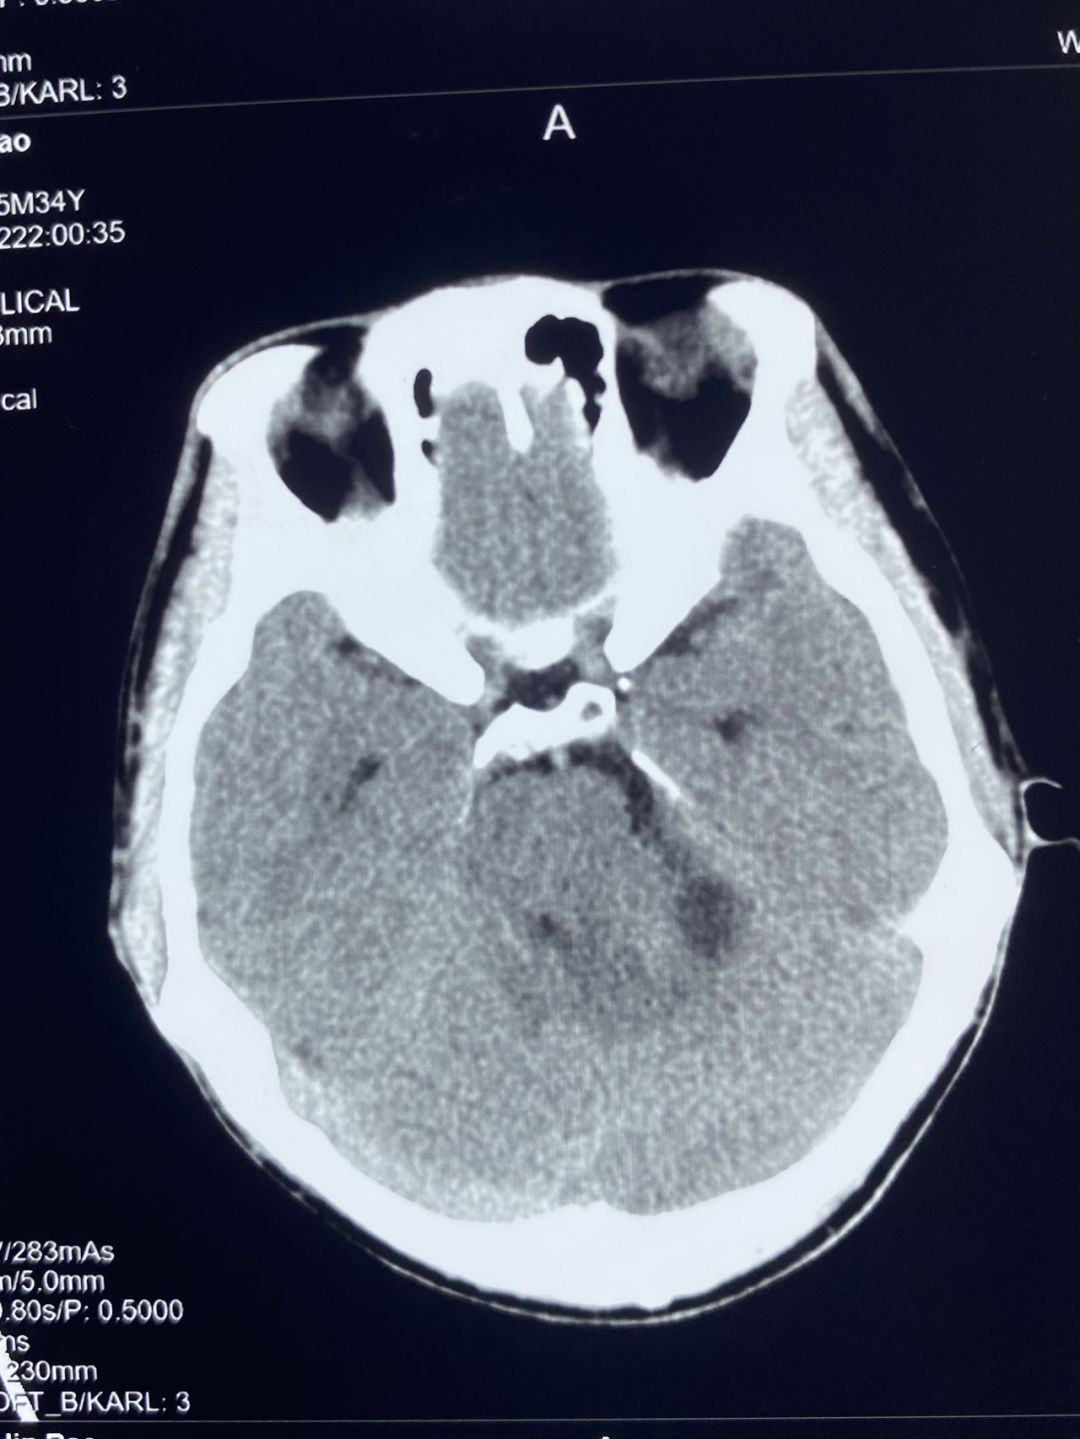

1、颅脑 CT 平扫

颅脑 CT 平扫显示左侧桥小脑角区可见团块状异常密度,大小约 3.0*3.4 cm,边界不清,内部密度欠均匀,可见低密度坏死区,左侧内听道较对侧扩大,邻近小脑受压。

诊断:左侧桥小脑角区占位,建议进一步检查。